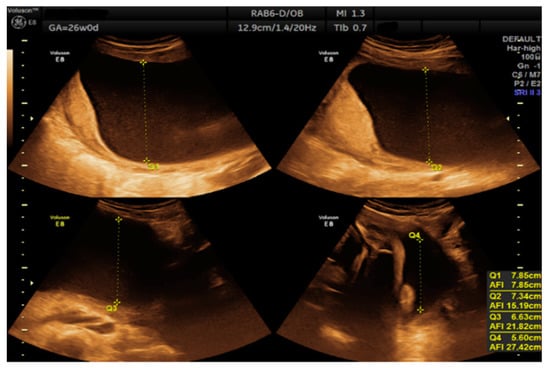

- Morphological examination during the 2nd trimester highlights the normal anatomy of the fetus (Figure 3).